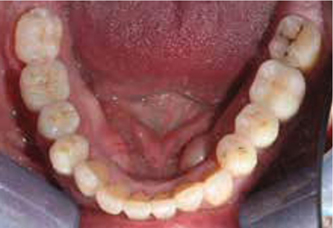

Bij het extraoraal onderzoek zie ik een lichte hypertrofie van de m. masseter. Intraoraal tref ik een ernstig versleten dentitie aan waarbij de slijtage niet passend bij de leeftijd kan worden genoemd (afbeelding 2-7 en tabel 1) .

Afb. 4

Occlusaal aanzicht van de onderkaak.

Afbeelding vergroten